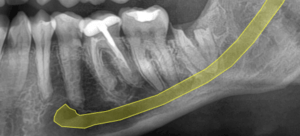

Radiografía de control postoperatorio al año, se evidencia desplazamiento de las raíces.